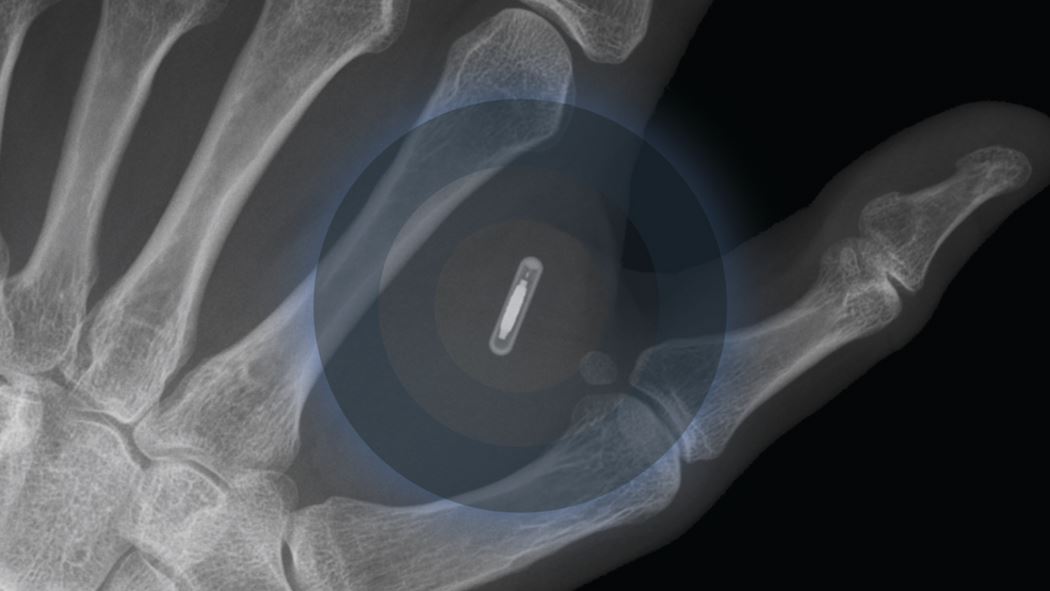

کۆمپانیایەکی سوێدی دەستی بە هەنگاوێکی نوێ کردووە کە دانانی مایکرۆچیپە لەژێر پێستی مەچەک و بەرپرسانی کۆمپانیاکەش دەڵێن، ئەو کارە لە هەڵگرتنی کارتی ڤاکسین ئاسانتر و باشترە.

هانس ژۆبلات، بەڕێوەبەری کۆمپانیای دانەری مایکرۆچیپ دەڵێت، "چیپێکم لەژێر پێستی دەستم داناوە و بە جۆرێک پرۆگرامم کردووە کە زانیارییەکانی پەیوەست بە وەرگرتنی ڤاکسینمی تێدایە، دەمەوێت بەردەوام ئەو زانیارییانەم لەبەردەستدا بن."

هانس ژۆبلات، باسی لەوەکرد، "تەنیا پێویستە مۆبایلەکەم لەسەر دەستم دابنێم و ئیدی خۆی دەکرێتەوە و فایلێکی pdf نیشاندەدات کە پاسپۆرتی ڤاکسینەکەمە، ئەوەش وادەکات بچمە هەر شوێنێک تەنانەت ئەگەر مۆبایلەکەشم پێنەبێت خەڵک دەتوانن بە مۆبایلەکانی خۆیان پاسپۆرتی ڤاکسینەکەم ببینن."

هانس ژۆبلات، بەڕێوەبەری کۆمپانیای دانەری مایکرۆچیپ گوتیشی، "دانانانی مایکرۆچیپێکی پێشکەوتوو لەژێر پێست تەنیا چەند سەت یۆرۆیەکی تێدەچێت، ئەوە لە کاتێکدایە کڕینی کاژێرێک کە باری تەندروستی دەخوێنێتەوە، تێچووەکەی دوو هێندەی دانانی مایکرۆچیپەکەیە. خەڵک دەتوانن مایکرۆچیپەکە نزیکەی 40 ساڵ بەکاربهێنن، بەڵام کاژێرەکە تەنیا دەتواندرێت بۆ ماوەی سێ تاوەکو چوار ساڵ لەدەست بکرێت."

ئامانج لە دانان و بەکارهێنانی مایکرۆچیپ ئەوەیە کە هاووڵاتییان پێویستیان بە هەڵگرتنی کارت و پاسپۆرتی ڤاکسین نەبێت، لە سوێد جگە لە کارتی ڤاکسین، مایکرۆچیپی تیکتی شەمەندەفەریش رێگەی پێدراوە و لە ساڵی 2017 ەوە کۆمپانیای نیشتمانیی هێڵی شەمەندەفەری سوێد کاری پێدەکات.